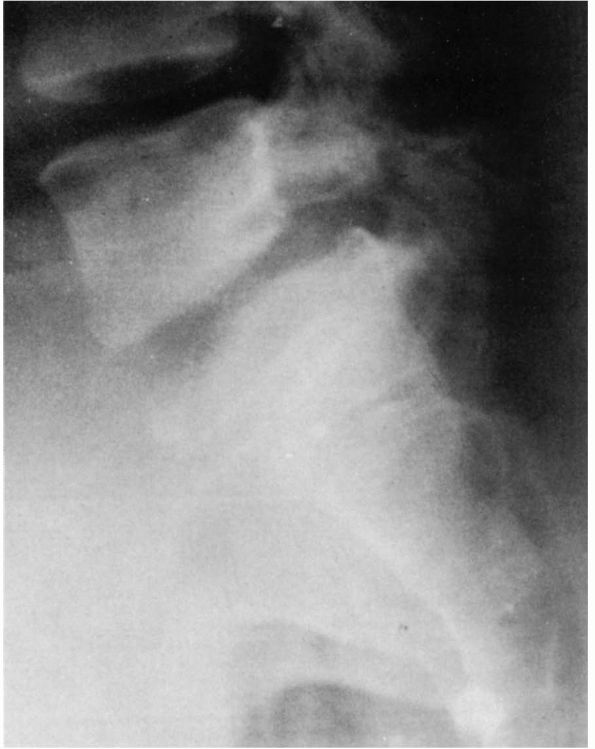

depending on the percentage of anterior translation of L5 on S1, with

grade 4, a complete slip (Figures 16-28 and 16-29). The term spondyloptosis

is used to describe complete displacement of L5 in front of S1. It is

important in assessing spondylolisthetic patients to have standing

lateral radiographs of the lumbosacral junction because instability is

not uncommon, particularly in childhood (Figure 16-28).